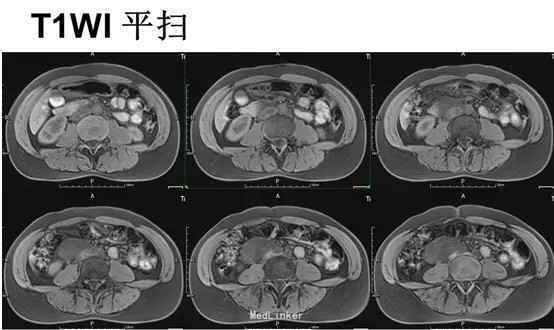

腹部平坦,未见胃肠型及蠕动波,无腹壁静脉曲张,腹软,下腹部轻度压痛,无反跳痛,下腹部扪及一包块,大小约7.5×6cm,质地硬,位置固定,移动性浊音阴性,肠鸣音正常。T 37.5°,P62次/分,R21次/分,Bp140/86mmHg。MR平扫及增强示:中下腹偏右侧见类圆形等长T1长T2异常信号,FS-T2WI呈高信号,DWI(b=800)呈高信号,相应ADC图呈低信号,边界尚清,周围组织受压但未受侵及,注入GD-DTPA后病变强化。

初步诊断:腹膜后肿瘤。行剖腹探查术+腹膜后肿瘤切除术。术后病理:(腹膜后)淋巴管肌瘤病。免疫组化:Vim +、SMA +、HMB-45 少数散在+、Ki-67 5%、MelanA -、ER -、PR -;扁平上皮:CD34 +、CD31部分+、D2-40灶性+。